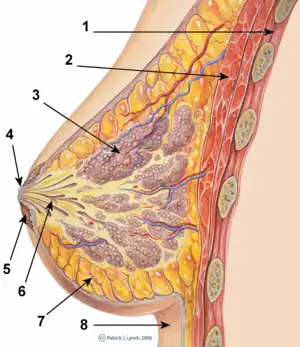

A breast implant is a prosthesis used to change the size, shape, and contour of a person's breast. In reconstructive plastic surgery, breast implants can be placed to restore a natural looking breast following a mastectomy, to correct congenital defects and deformities of the chest wall or, cosmetically, to enlarge the appearance of the breast through breast augmentation surgery.

In surgical practice, for the reconstruction of a breast, the tissue expander device is a temporary breast prosthesis used to form and establish an implant pocket for the future permanent breast implant. For the correction of male breast defects and deformities, the pectoral implant is the breast prosthesis used for the reconstruction and the aesthetic repair of a man's chest wall (see: gynecomastia and mastopexy).

Implant pocket placement

The five surgical approaches to emplacing a breast implant to the implant pocket are often described in anatomical relation to the pectoralis major muscle.

- Subglandular: the breast implant is emplaced to the retromammary space, between the breast tissue (the mammary gland) and the pectoralis major muscle (major muscle of the chest), which most approximates the plane of normal breast tissue, and affords the most aesthetic results. Yet, in women with thin pectoral soft-tissue, the subglandular position is likelier to show the ripples and wrinkles of the underlying implant. Moreover, the capsular contracture incidence rate is slightly greater with subglandular implantation.

- Subfascial: the breast implant is emplaced beneath the fascia of the pectoralis major muscle; the subfascial position is a variant of the subglandular position for the breast implant.[90] The technical advantages of the subfascial implant-pocket technique are debated; proponent surgeons report that the layer of fascial tissue provides greater implant coverage and better sustains its position.[91]

- Subpectoral (dual plane): the breast implant is emplaced beneath the pectoralis major muscle, after the surgeon releases the inferior muscular attachments, with or without partial dissection of the subglandular plane. Resultantly, the upper pole of the implant is partially beneath the pectoralis major muscle, while the lower pole of the implant is in the subglandular plane. This implantation technique achieves maximal coverage of the upper pole of the implant, whilst allowing the expansion of the implant's lower pole; however, "animation deformity", the movement of the implants in the subpectoral plane can be excessive for some patients.[92]

- Submuscular: the breast implant is emplaced beneath the pectoralis major muscle, without releasing the inferior origin of the muscle proper. Total muscular coverage of the implant can be achieved by releasing the lateral muscles of the chest wall—either the serratus muscle or the pectoralis minor muscle, or both—and suturing it, or them, to the pectoralis major muscle. In breast reconstruction surgery, the submuscular implantation approach effects maximal coverage of the breast implants. This technique is rarely used in cosmetic surgery due to high risk of animation deformities.

- Prepectoral or subcutaneous: in a breast reconstruction following a skin-sparing or skin- and nipple-sparing mastectomy, the implant is placed above the pectoralis major muscle without dissecting it so that the implant fills directly the volume of the mammary gland that has been removed. To avoid the issue of capsular contracture, the implant is often covered frontally or completely with a mesh in biomaterial, either biological or synthetic.